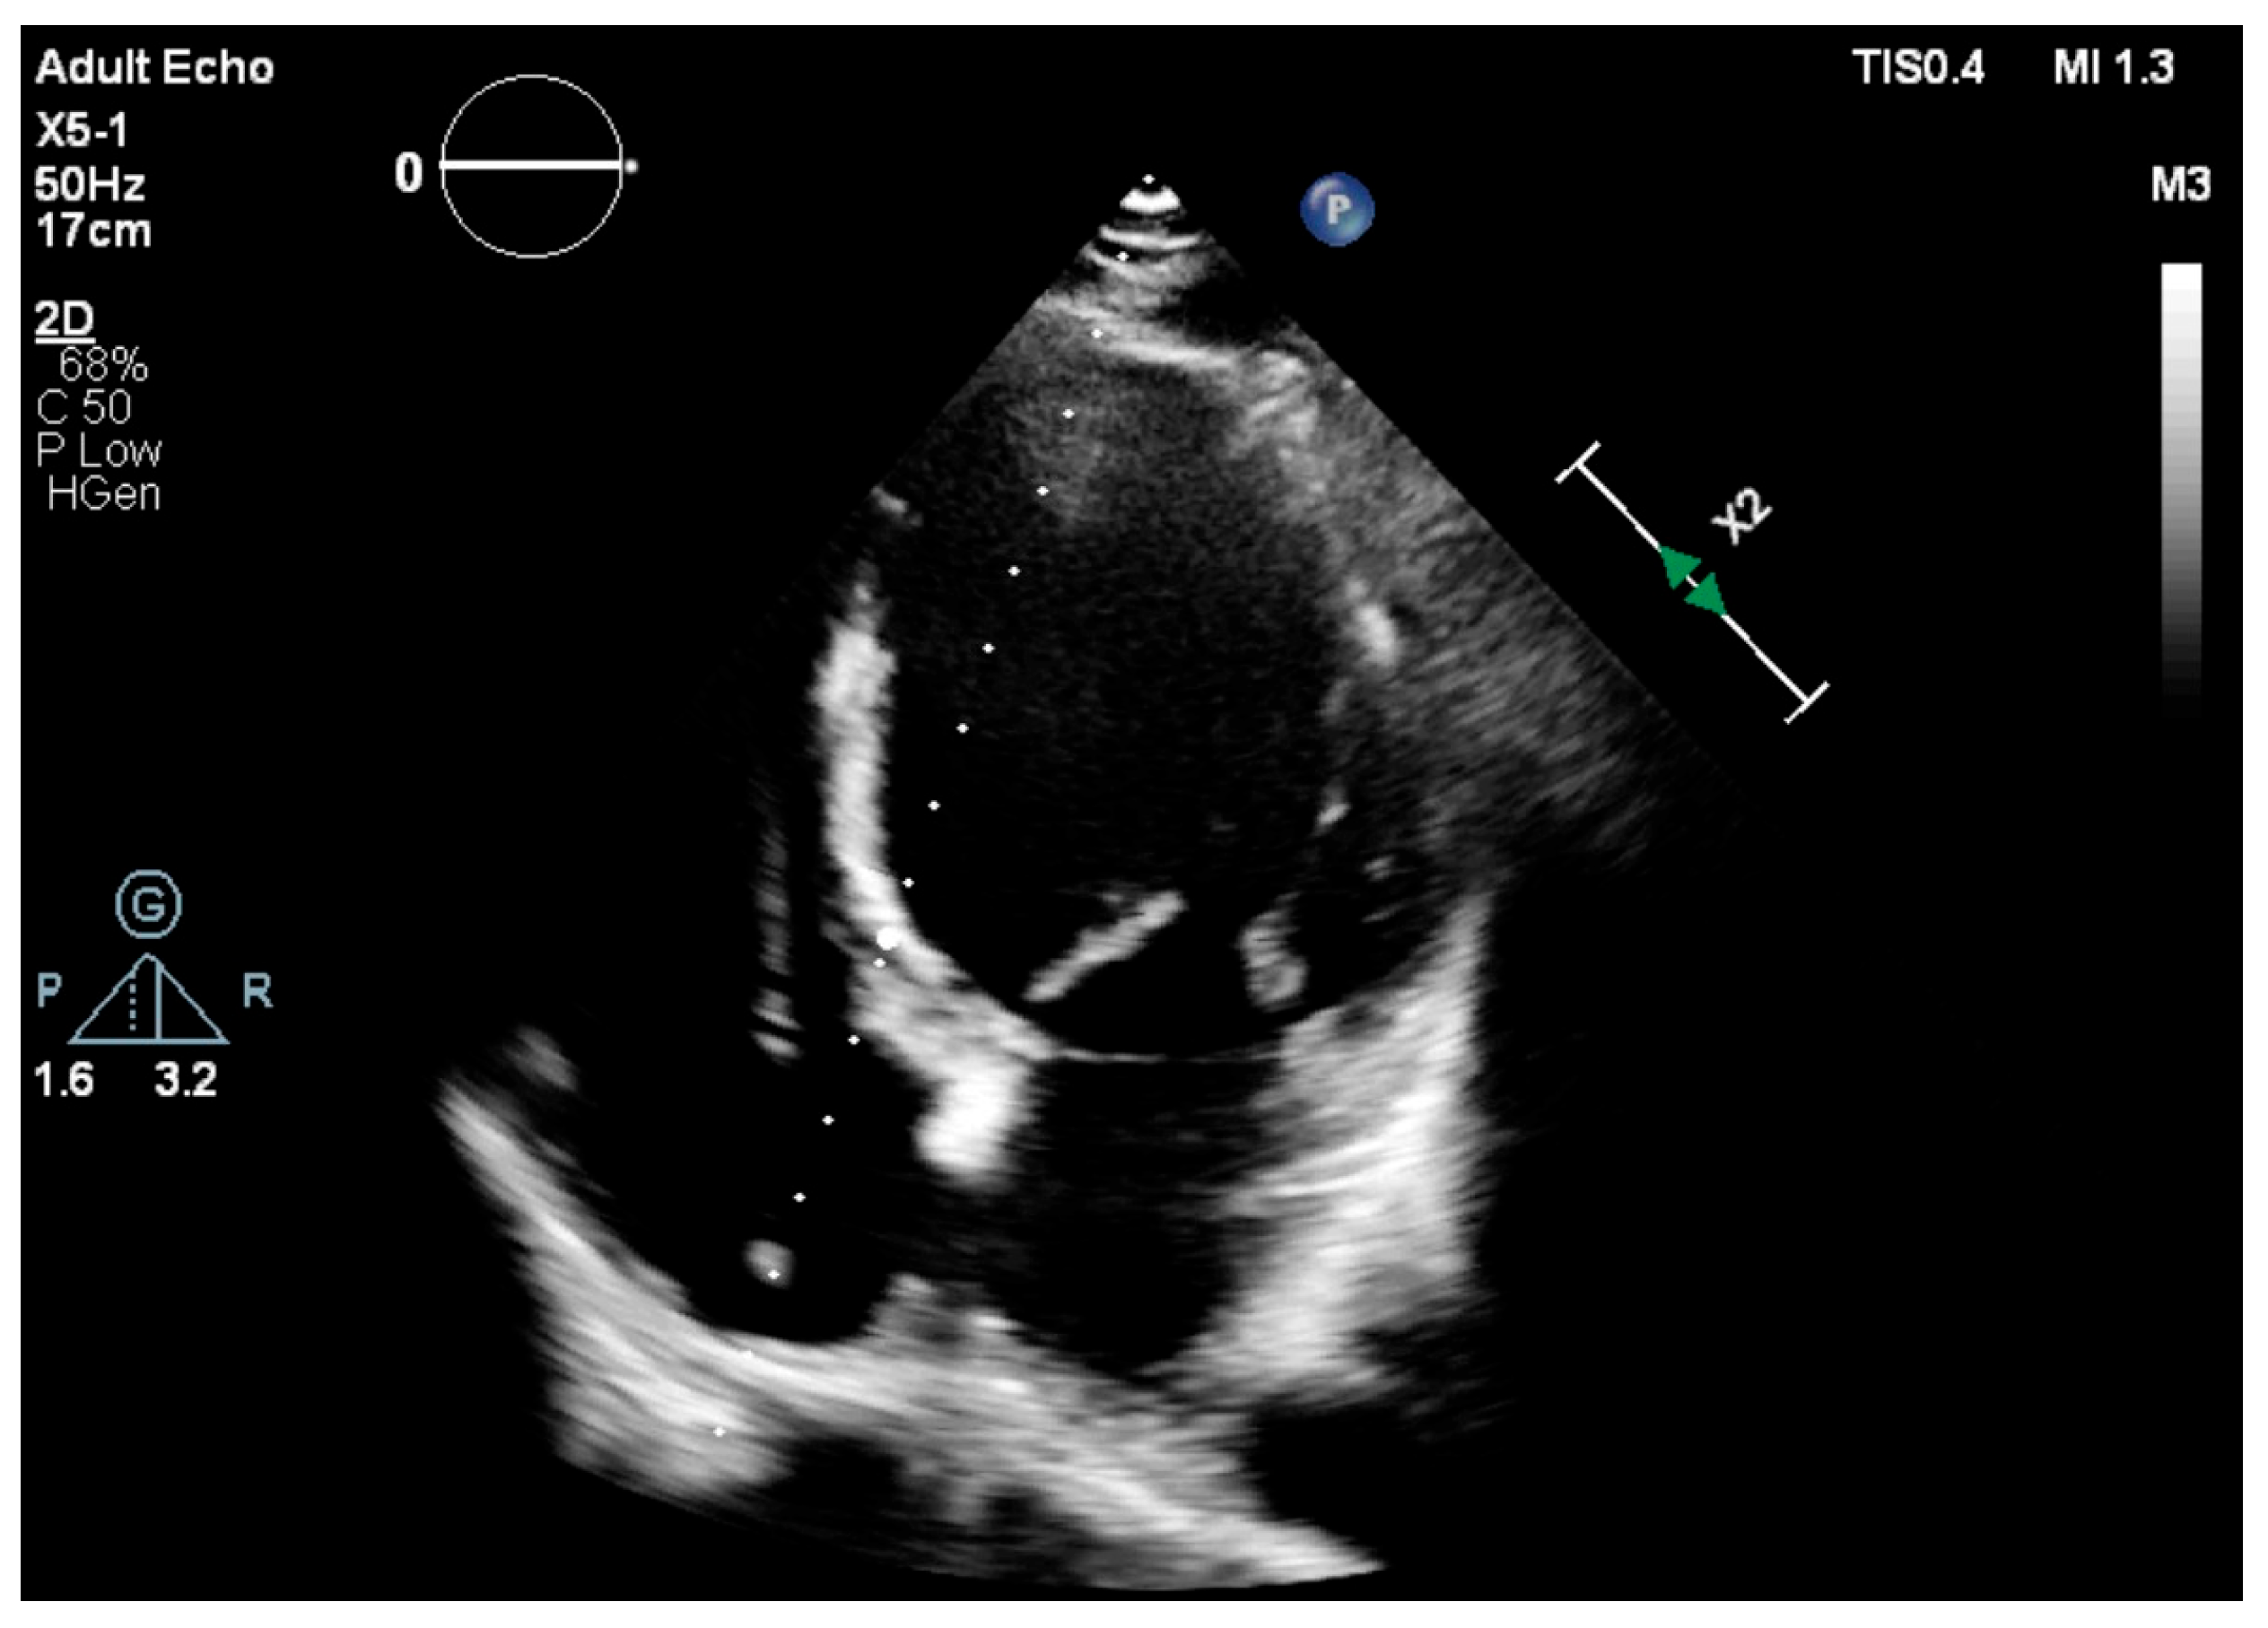

2.3. Echocardiographic Assessment

| Avg MAPSE (mm) | 13.65 | 2.05 |

| Septal MAPSE (mm) | 13.15 | 2.02 |

| Lateral MAPSE (mm) | 14.16 | 1.97 |

| Average MAPSE | 0.89 | <0.001 |

| Septal MAPSE | 0.90 | |

| Lateral MAPSE | 0.88 |